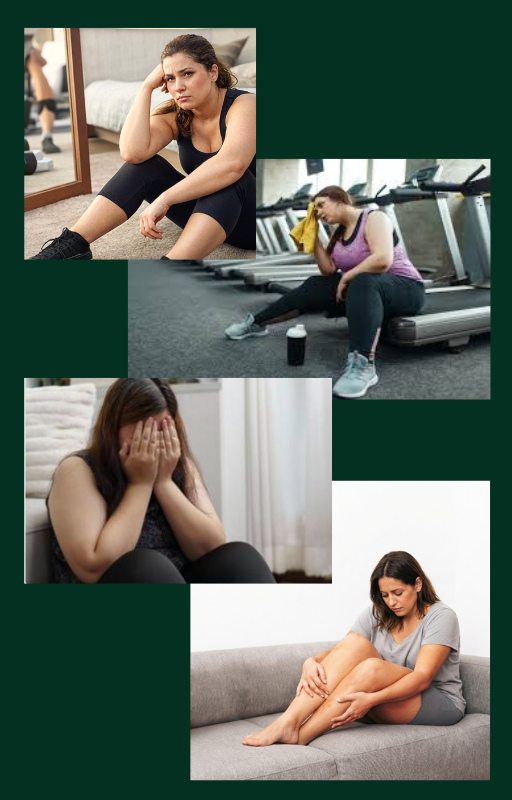

Você já tentou emagrecer, treinar e se esforçar, mas seu corpo simplesmente não responde?

Afeta majoritariamente mulheres, causando dor, sensibilidade ao toque, inchaço, hematomas frequentes e sensação de peso, não respondendo bem a dietas ou exercícios.

O problema nunca foi você!